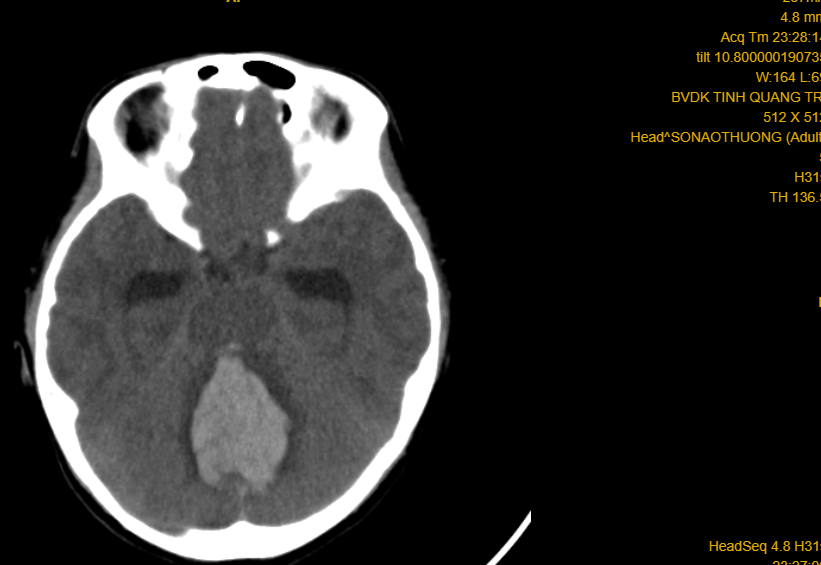

Phim CT-scan trường hợp số 02 (cháu gái 10 tuổi) xuất huyết não